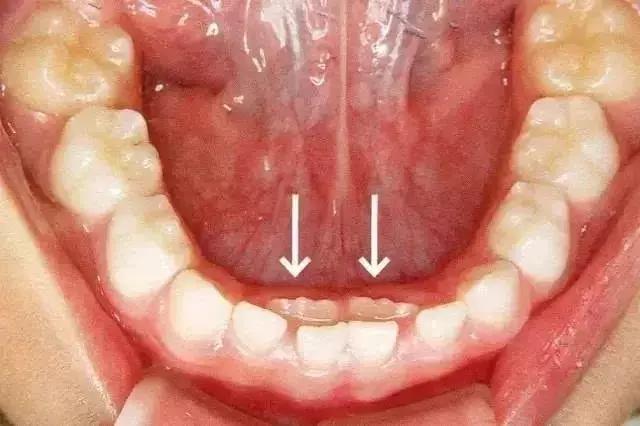

这种孩子乳牙还没脱落,新牙就长出来的现象,就是所谓的“双排牙”现象。也就是医生常说的“乳牙滞留”。

箭头所指为恒牙